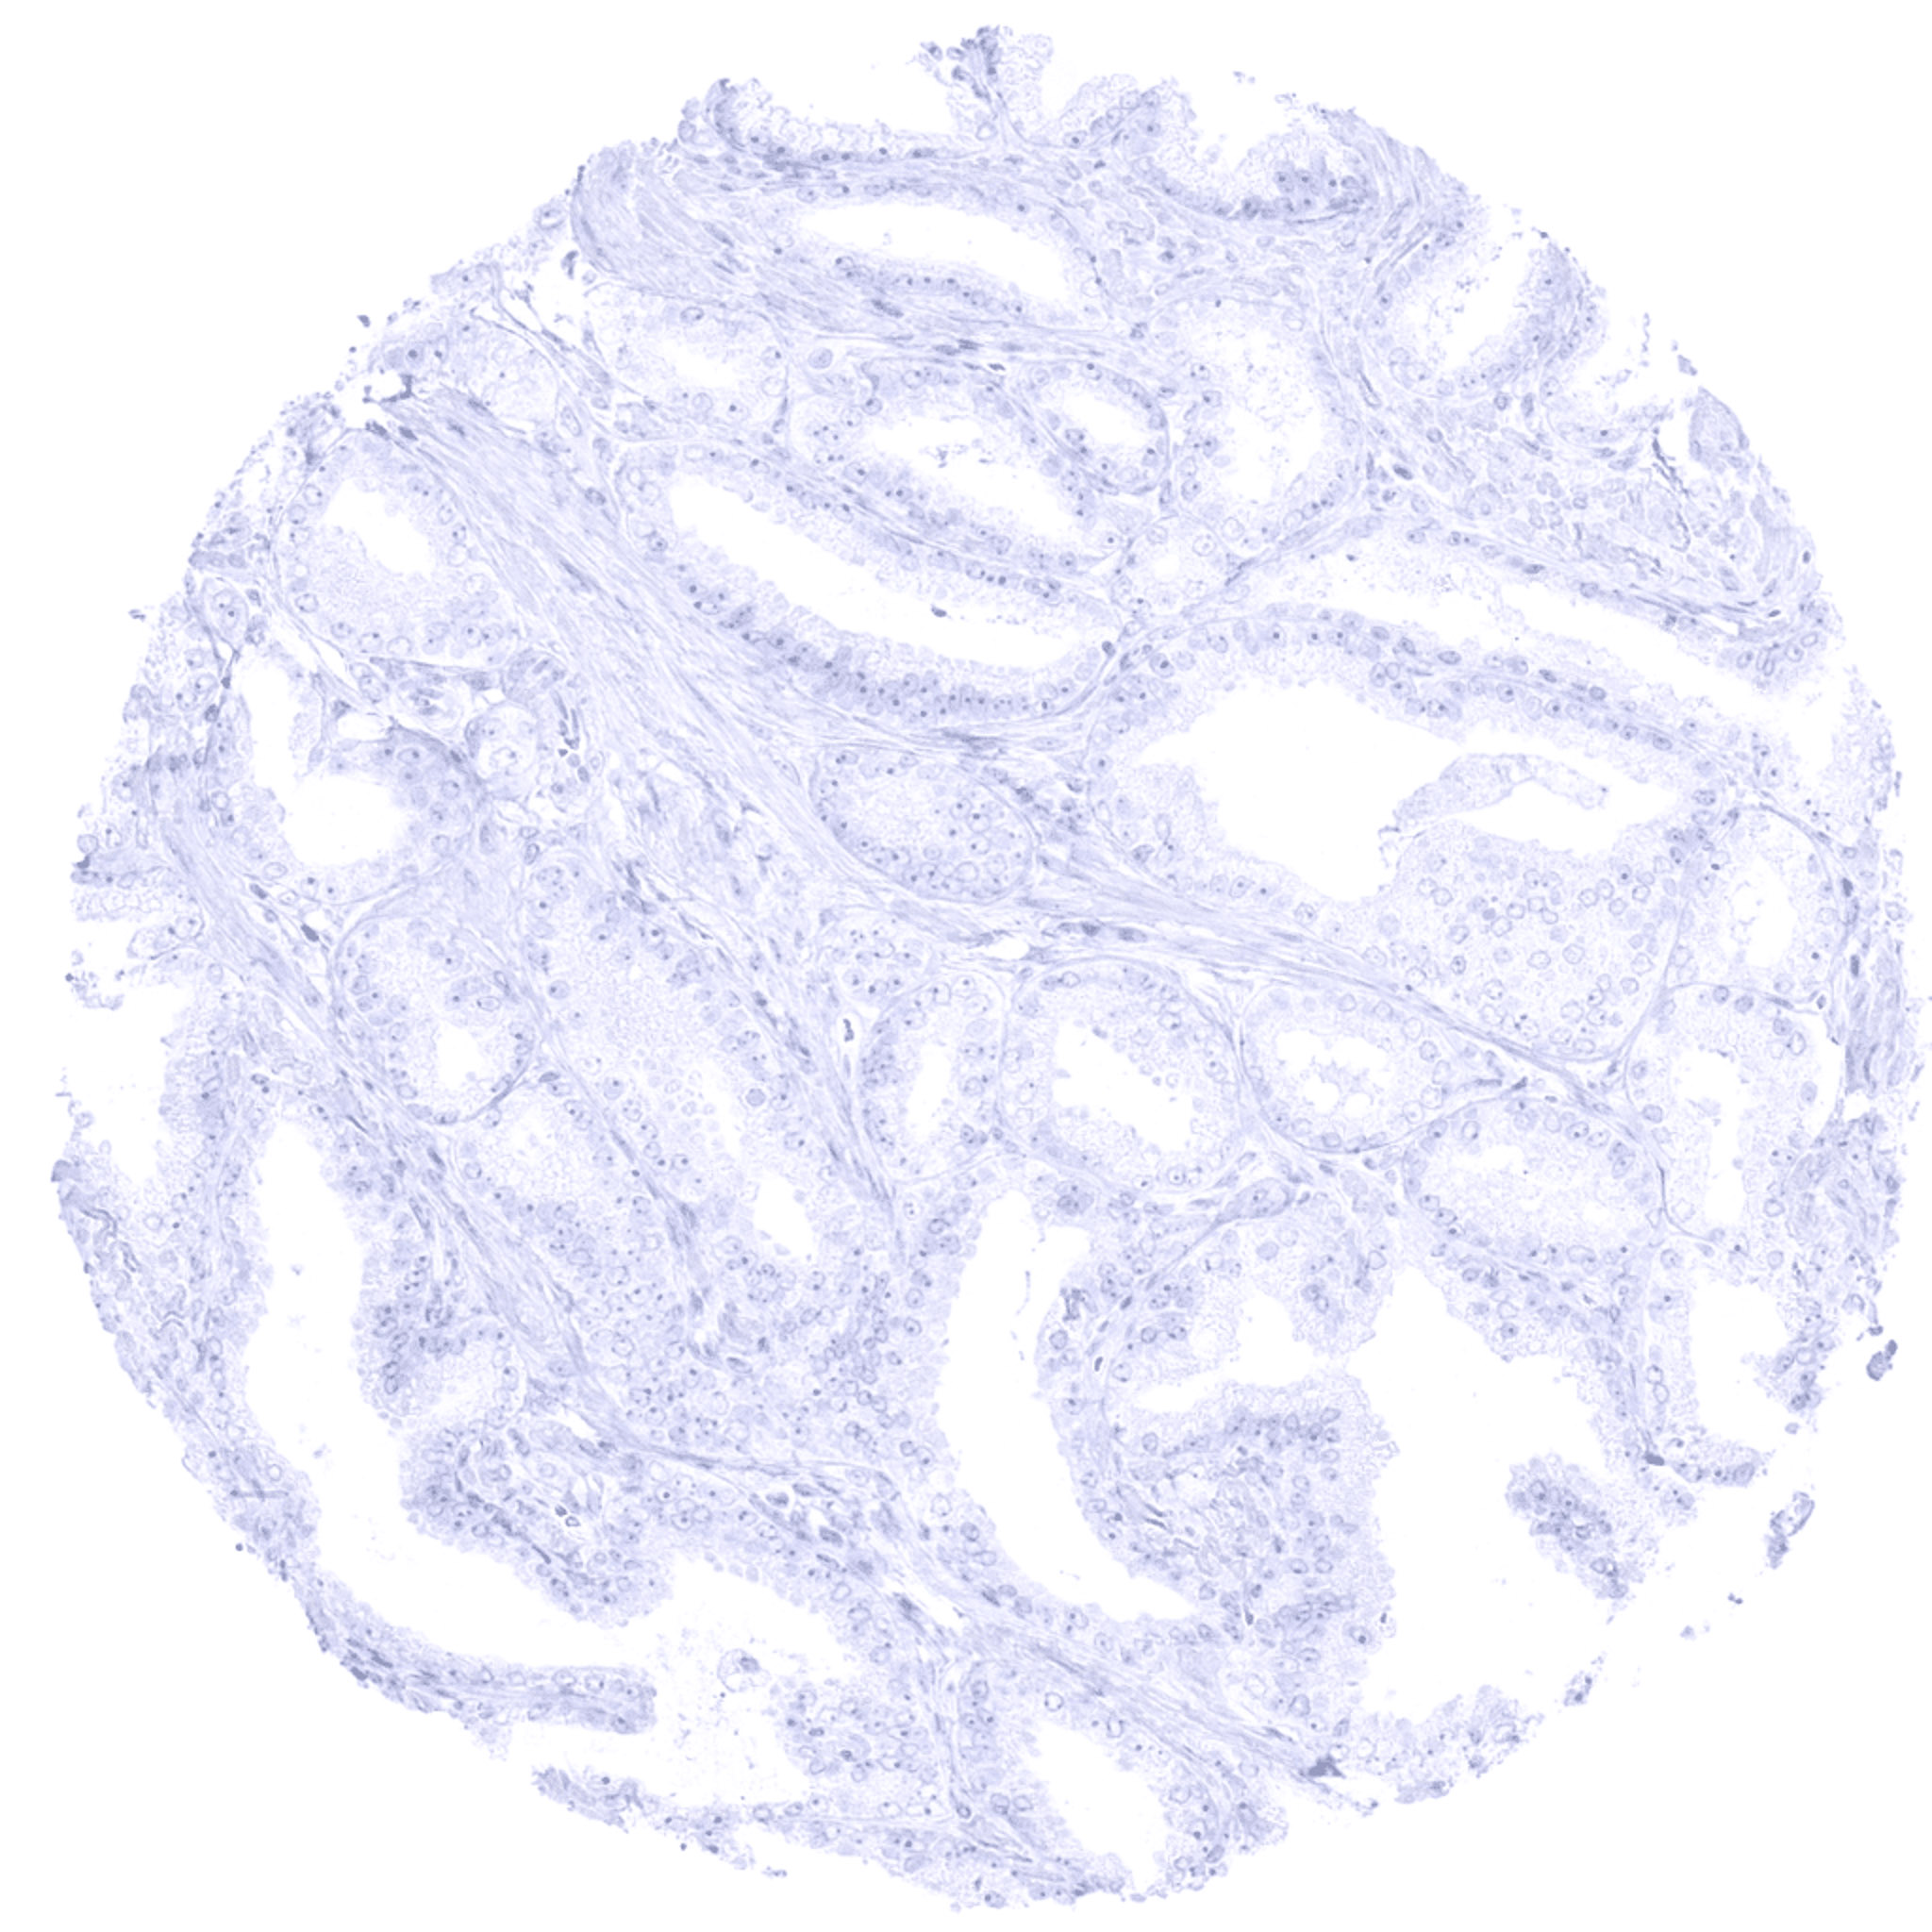

Urinary bladder- Non-invasive urothelial carcinoma (low grade, pTaG2) with strong S100P immunostaining of tumor cells.